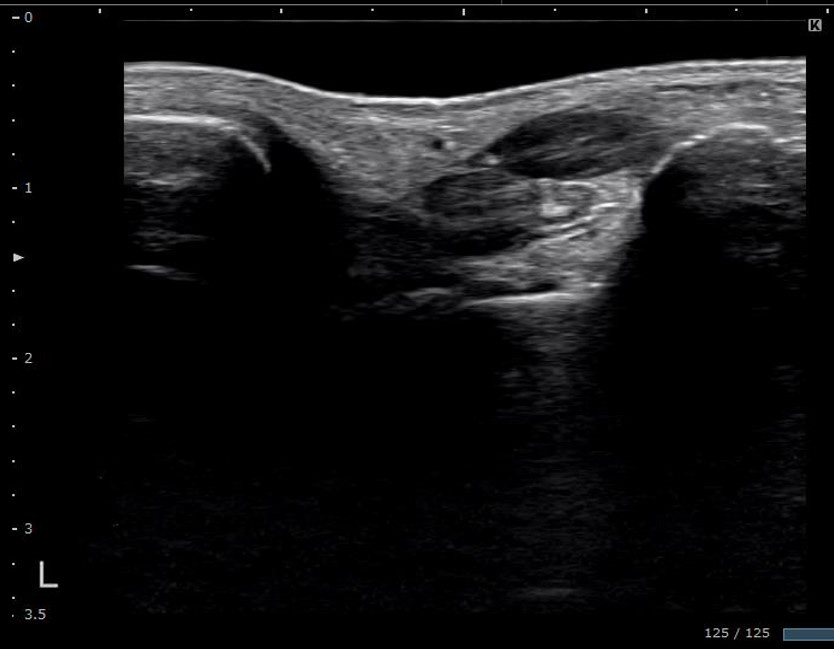

エコーゲルパッドで凹部の描出

| エコーゲルパッド | EP-S-10(10mm) |

| 診断装置 | コニカミノルタ社製 SONIMAGE HS2 |

| プローブ | L18-4 |

監修 わだ整形外科クリニック 和田誠先生